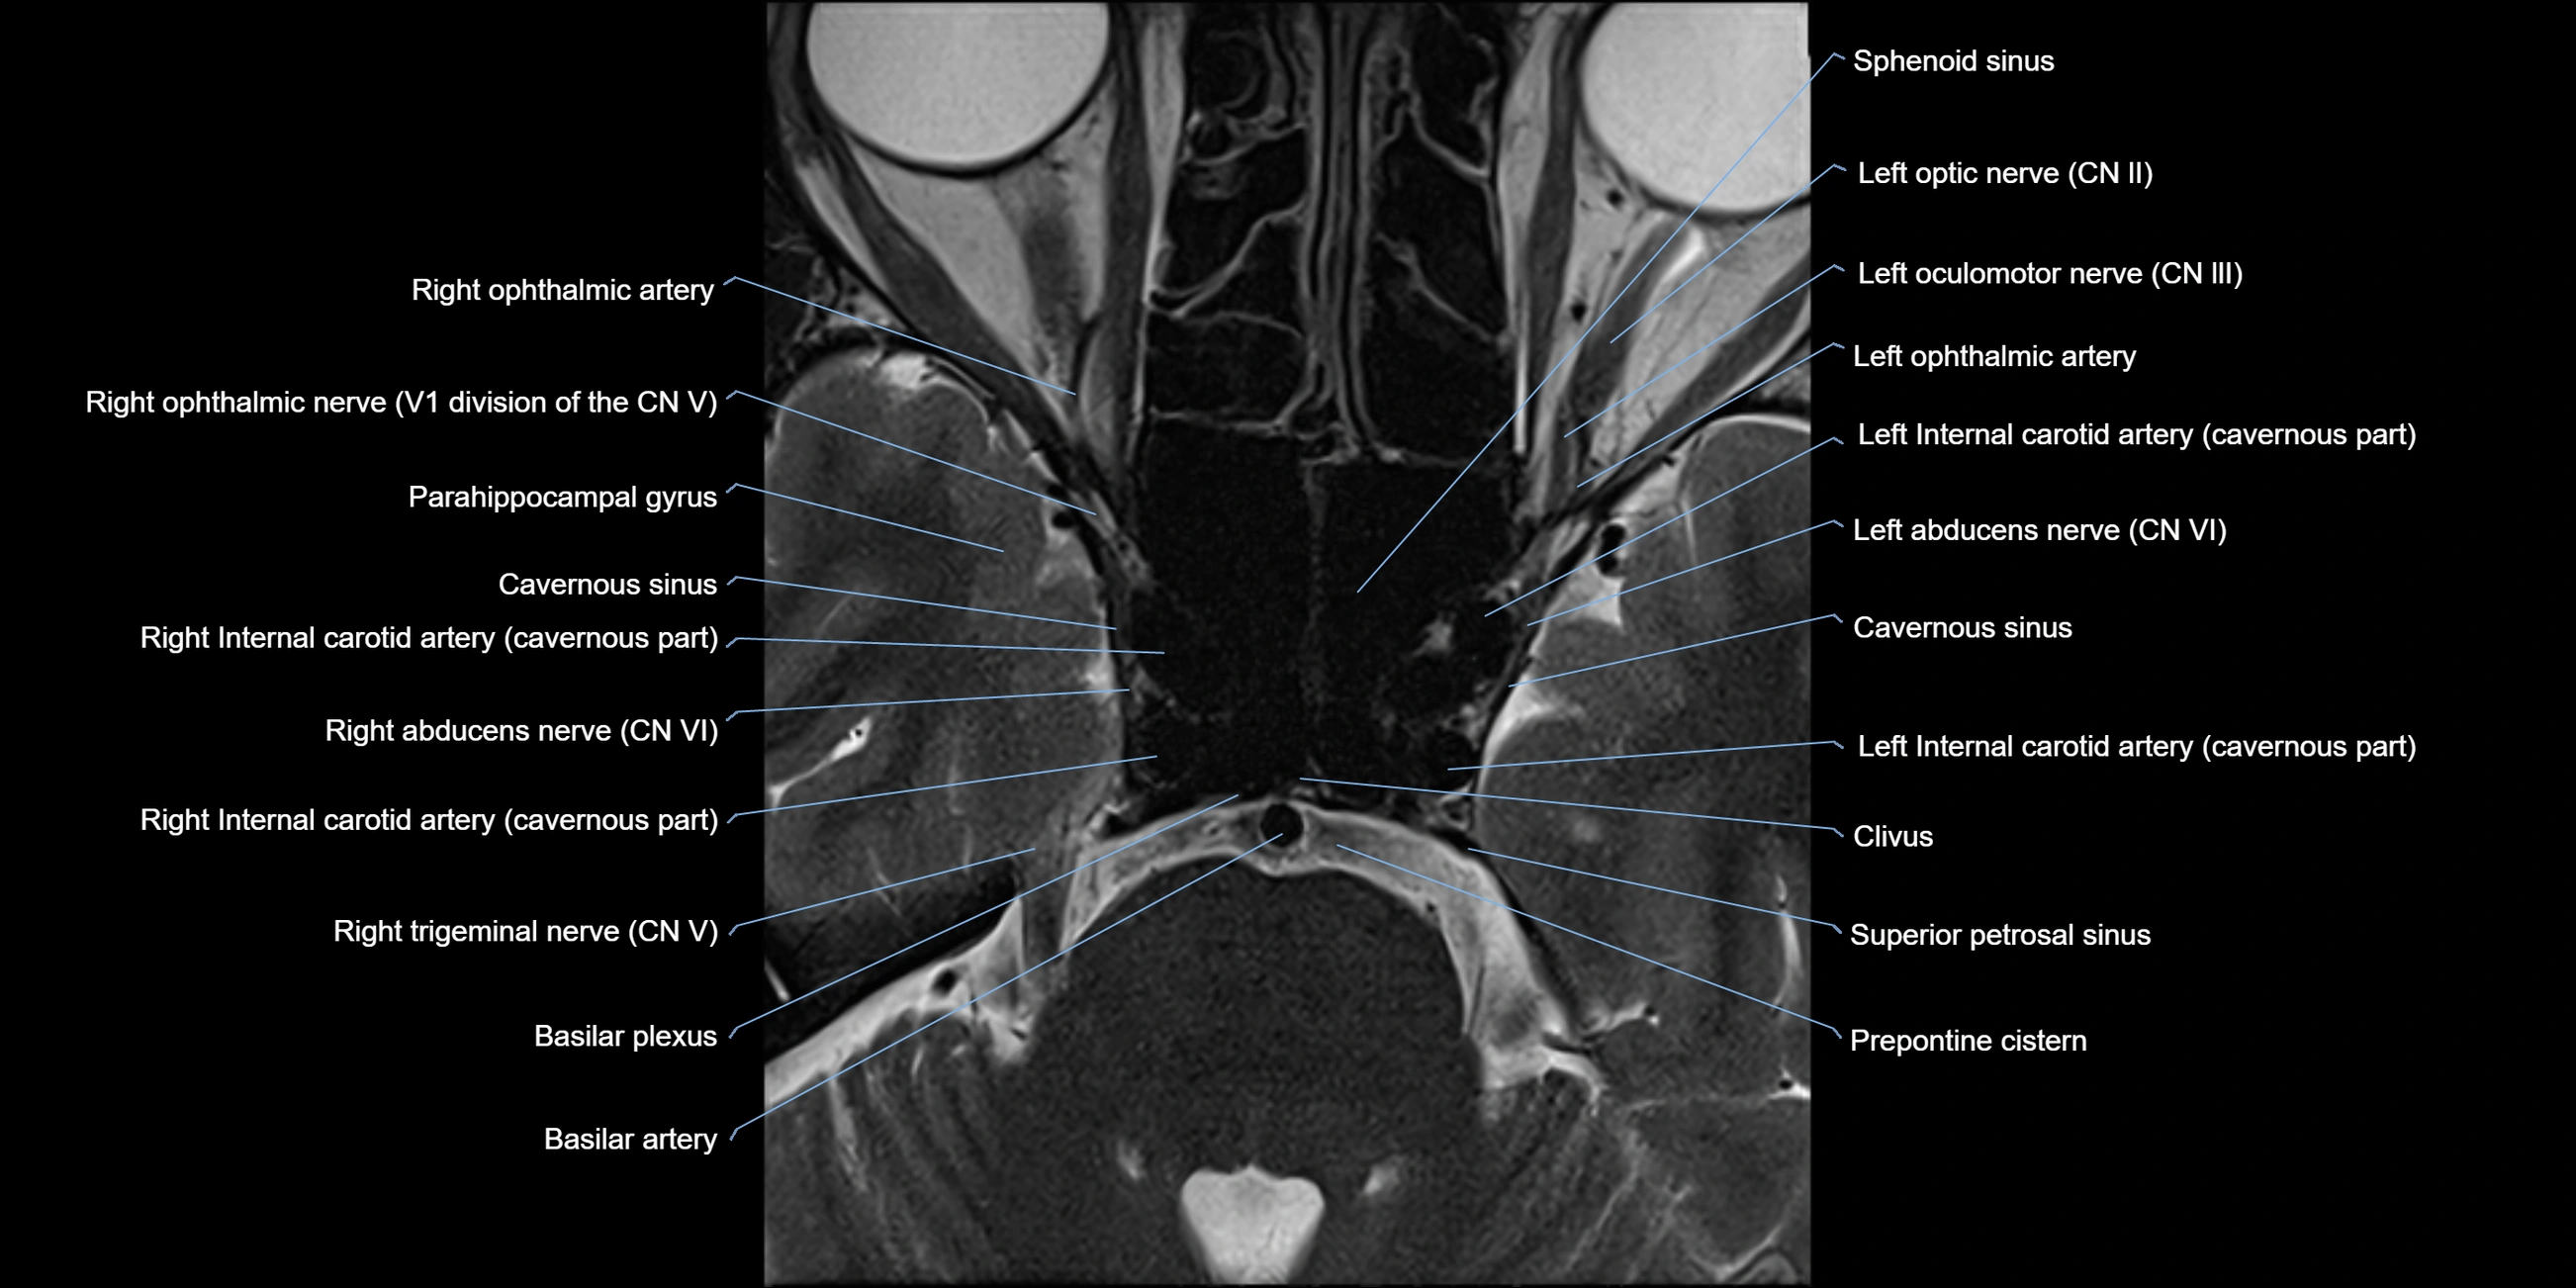

MRI Appearance

The abducens nerve is a small, thin, linear structure

Best visualized on high-resolution T2-weighted 3D MRI sequences (e.g., FIESTA or CISS)

Seen as a hypointense (dark) line running from the brainstem at the pontomedullary junction, traversing the prepontine cistern, and entering Dorello’s canal under the petrosphenoidal ligament, then into the cavernous sinus, and finally the orbit

May be challenging to visualize in standard MRI due to its small size

Pathology may be inferred by absence, displacement, or enhancement of the nerve